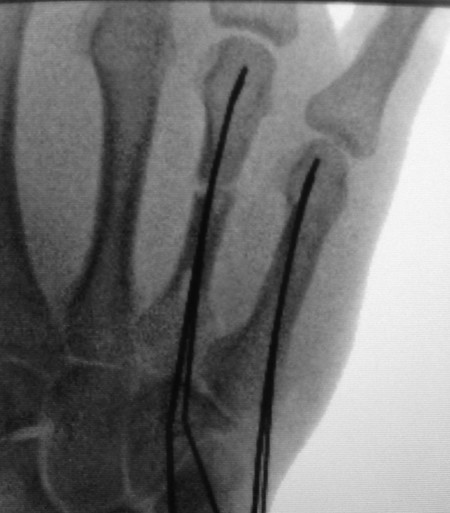

Percutaneous K-wire fixation should be considered in many closed hand fracture configurations, where a satisfactory closed reduction has been achieved, but is unlikely to be maintained with splints or casts alone (Fig. 14‑7). However, K-wiring is not always easy to perform and sometimes multiple passes are made in error. To minimize problems, a number of simple steps can be performed.

One must mark the joints with a pen to help with the 3D understanding of the fracture. Radiologic markers such as a 25-gauge orange needle can help guide the trajectory of the K-wire (Fig. 14‑8, Fig. 14‑9). However, when passing the K-wire one should go by feeling the resistance of the cortical bone. Furthermore, making small stab incisions through the skin with a 15 blade is useful rather than stabbing the K-wire through the skin inadvertently catching the extensor mechanism. If repeated attempts are made during surgery, a new K-wire should be loaded on the driver. Repeated attempts and high revolutions should be avoided as thermal damage to bone can result in problems with union and infection.